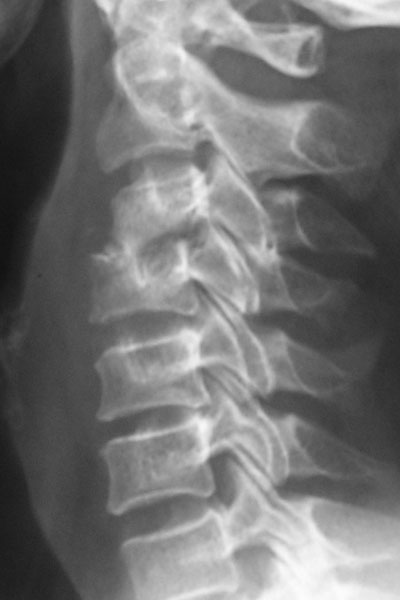

Craniovertebral Junction Anomaly

The junction of the skull with the neck is called craniovertebral junction. This is the site for a number of pathologies, that can have severe neurological problems and can be potentially life threatening. Diagnosis is achieved by CT and MRI, and treatment involves decompression and provision of stability by metallic implants.